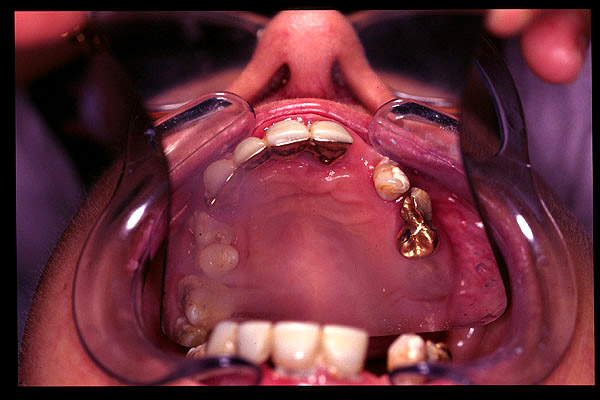

CM Diente dorado incluido en la prótesis parcial